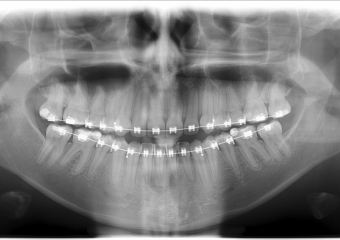

Rx panorâmico apos a cirurgia